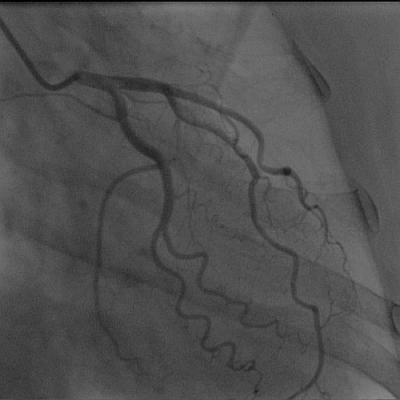

心臓(左冠動脈)

左冠動脈